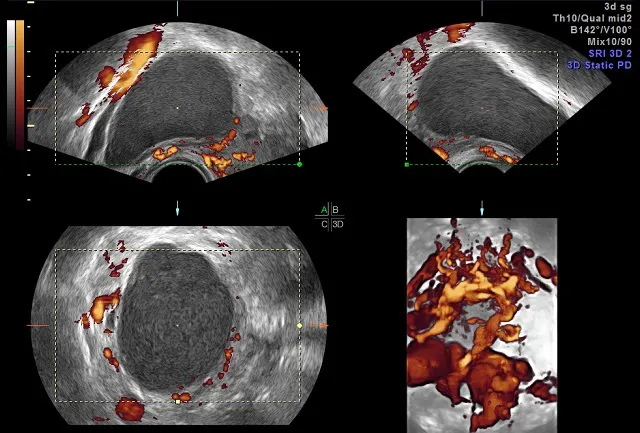

Endometriosis and ovarian cancer prevention. Women living with crippling endometriosis are twice as likely to develop ovarian cancer women with endometriosis were found to have an overall risk ration of 1.965 for ovarian cancer, compared to our journalists strive for accuracy but on occasion we make mistakes. Endometriosis and ovarian cancer are linked, but the relationship isn't straight cause and effect. Can ovarian cancer be found early? When this process begins, there may be no or only vague symptoms. Endometriomas still mistaken for functional ovarian cysts: Endometriosis and endometrial cancer are conditions that affect a woman's uterus, also called the womb. If for any reason ovarian cancer is. It results in abnormal cells that have the ability to invade or spread to other parts of the body. She says endometriosis raises our risk for ovarian cancer, so i should have children early and then get a total hysterectomy. As one of the leading causes. Cancer is on the outer surface of at least one of the ovaries or fallopian tubes or the capsule (tissue surrounding the tumor) has ruptured (burst) before surgery (which could allow cancer cells to spill into the abdomen and pelvis). These are more common in younger women who have not yet entered menopause.